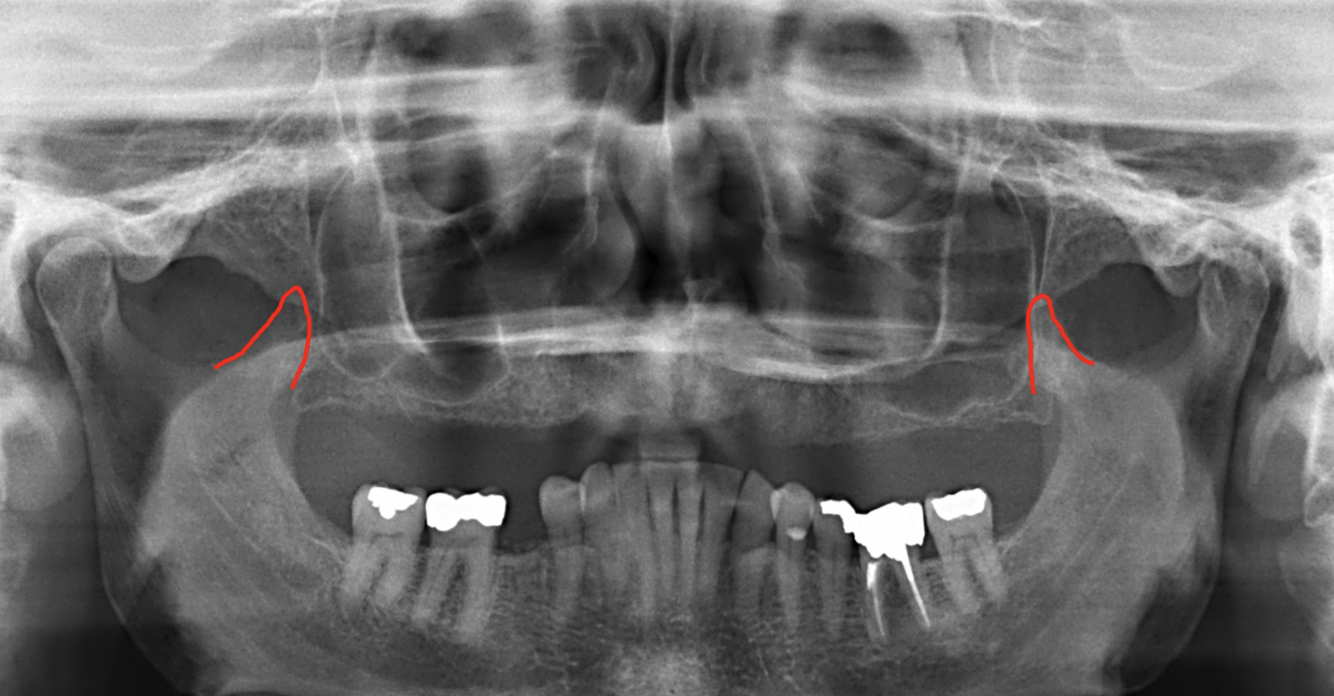

What is indicated by the red circles in the following image?

External auditory meatus